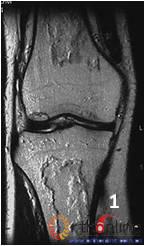

1. 单纯骨髓坏死。发生在长骨骨干及干骺端的坏死只累及骨髓组织,骨皮质很少受累,称为骨梗死(bone infarction)。坏死仅累及骨髓,不会累及皮质。(图2)

图2 男,40岁,激素相关骨梗死,MRI显示坏死仅累及骨髓,皮质存留:(1)股骨干和胫骨干冠状位图像;(2)股骨干和胫骨干矢状位图像;(3)股骨干横断面;(4)胫腓骨横断面

Fig 2 Male, 40 year-old, steroid-associated the bone infarction, MRI showed necrosis involved only in bone marrow, the cortical bone was preserved: (1) the coronal image of diaphysis of femur and tibia;(2) the saggital image of femur and tibia; (3) Transverse section of femur; (4) Transverse section of tibia